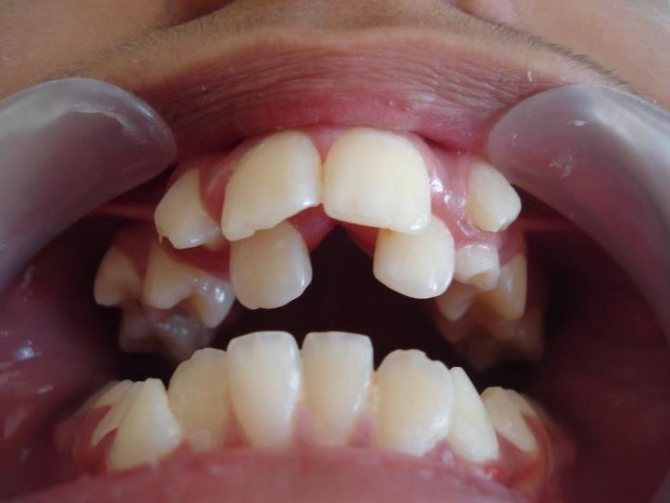

Проблема у пациентов диагностируется достаточно редко. Выделяют несколько форм патологий величины зубов. Микродентия характеризуется наличием мелких по сравнению с нормой элементов в ротовой полости. Проблема наблюдается в двустороннем порядке, реже проявляется с одной стороны челюсти. При микродентии элементы отличаются неправильной формой.

В стоматологии микродению подразделяют еще на несколько форм: изолированную, относительную и генерализованную. В первом случае обнаруживается 1-2 зуба, которые имеют аномальные размеры. Чаще всего видоизменяются боковые резцы. При относительном типе проблемы зубы имеют нормальные размеры, но из-за больших пропорций челюсти визуально кажутся маленькими. Генерализованная микродентия – наличие мелких единиц по всей длине челюсти.

Микродентия – мелкие зубы, размеры их меньше среднестатистических параметров. Диагностируется визуально, чаще всего у боковых и верхних резцов. Зубы растут с большими промежутками и являют собой достаточно серьезную проблему эстетического характера.

Малый размер (микродентия) предполагает слишком большие межзубные промежутки. Такая патология ухудшает внешний вид. Лечение проводится путем установки новых коронок.

Микродентия относится к заболеваниям, характеризующимся прорезыванием постоянных зубов с аномальным развитием их размеров.

При данной патологии, они имеют меньшие размеры не только в диаметре, но и высоте, хотя высота, чаще, всего лишь незначительно отличается от среднестатистической нормы.

В основном, патология охватывает зубы переднего или бокового отдела, но может поражать и весь зубной ряд. Особенно подвержены заболеванию боковые и центральные резцы.

Как правило, для микродентии характерна асимметричность, но и здесь существуют свои исключения.